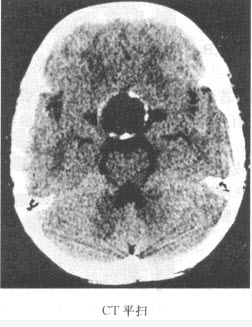

2、单项选择题 患者,女,80岁,被人发现昏迷,大小便失禁10小时入院。体格检查:血压180/100mmHg,心率约110次/分,有房颤,体温37℃,浅昏迷,右侧肢体未见自主活动,肌力增高,Babinski征阳性,GCS=E2+V1+M3=6分,有风湿性心脏病和房颤病史,既往超声检查有二尖瓣赘生物。

患者检查图像如下,你考虑何种疾病()

1、多项选择题 患者,女,80岁,被人发现昏迷,大小便失禁10小时入院。体格检查:血压180/100mmHg,心率约110次/分,有房颤,体温37℃,浅昏迷,右侧肢体未见自主活动,肌力增高,Babinski征阳性,GCS=E2+V1+M3=6分,有风湿性心脏病和房颤病史,既往超声检查有二尖瓣赘生物。 你的诊断依据是哪些()

A.昏迷伴大小便失禁10小时

B.CT示脑实质内大面积均匀低密度区

C.脑实质内见类圆形密度增高影,边缘见大面积低密度区

D.脑内占位性病变,瘤周水肿明显

E.脑沟、脑池增宽,密度与脑脊液密度相似

F.CT示脑实质内低密度区不强化